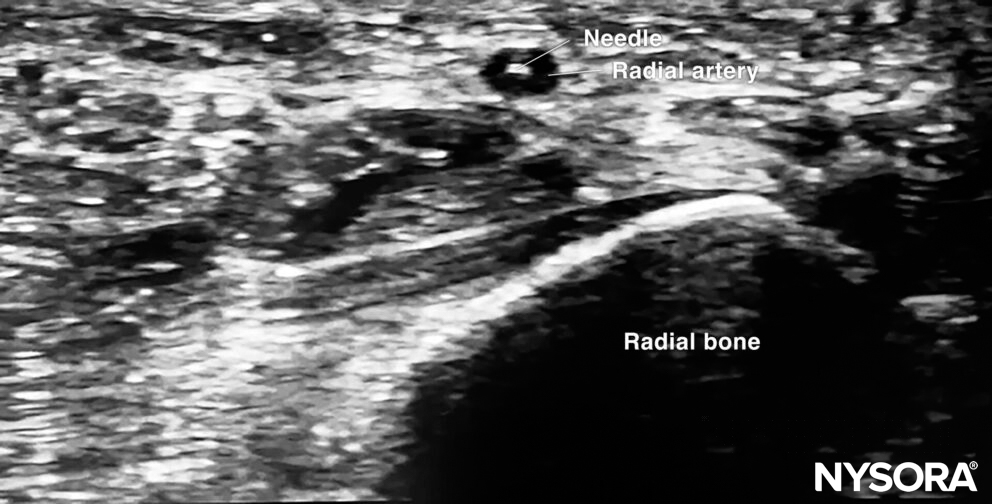

The out-of-plane technique is the most commonly used technique for arterial vascular access. Before the actual puncture, scan dynamically to get an idea about the direction of the artery. Use the creep technique to follow the needle tip at all times.

Out-of-plane cannulation of the radial artery